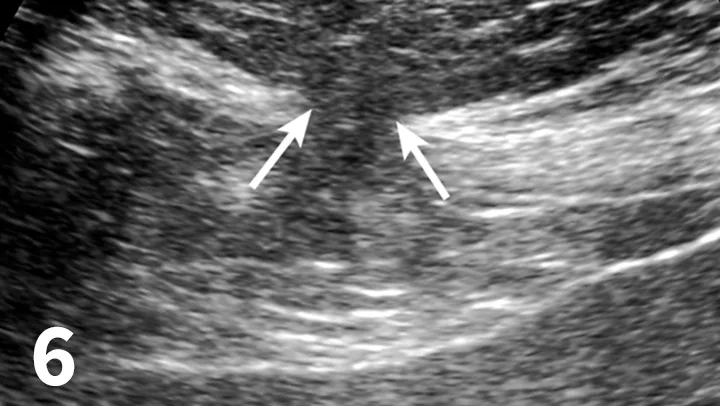

• CT and ultrasound may help differentiate a fluid pocket from presumed cellulitis or help locate an abdominal wall defect (Figure 6).

Featured Image

FIGURE 6

Ultrasound reveals a focal defect within the linea alba (arrows). Intra-abdominal fat extends through the defect into the subcutaneous tissues.